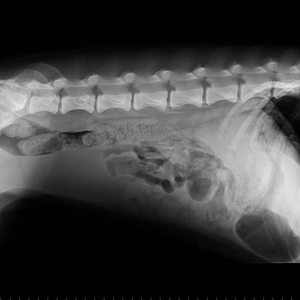

Centrul Medical Veterinar Colentina Vet oferă posesorilor de animale de companie o gamă variată de

consultații de specialitate și administrare tratamente pentru membrul blănos al familiei dumneavoastră.